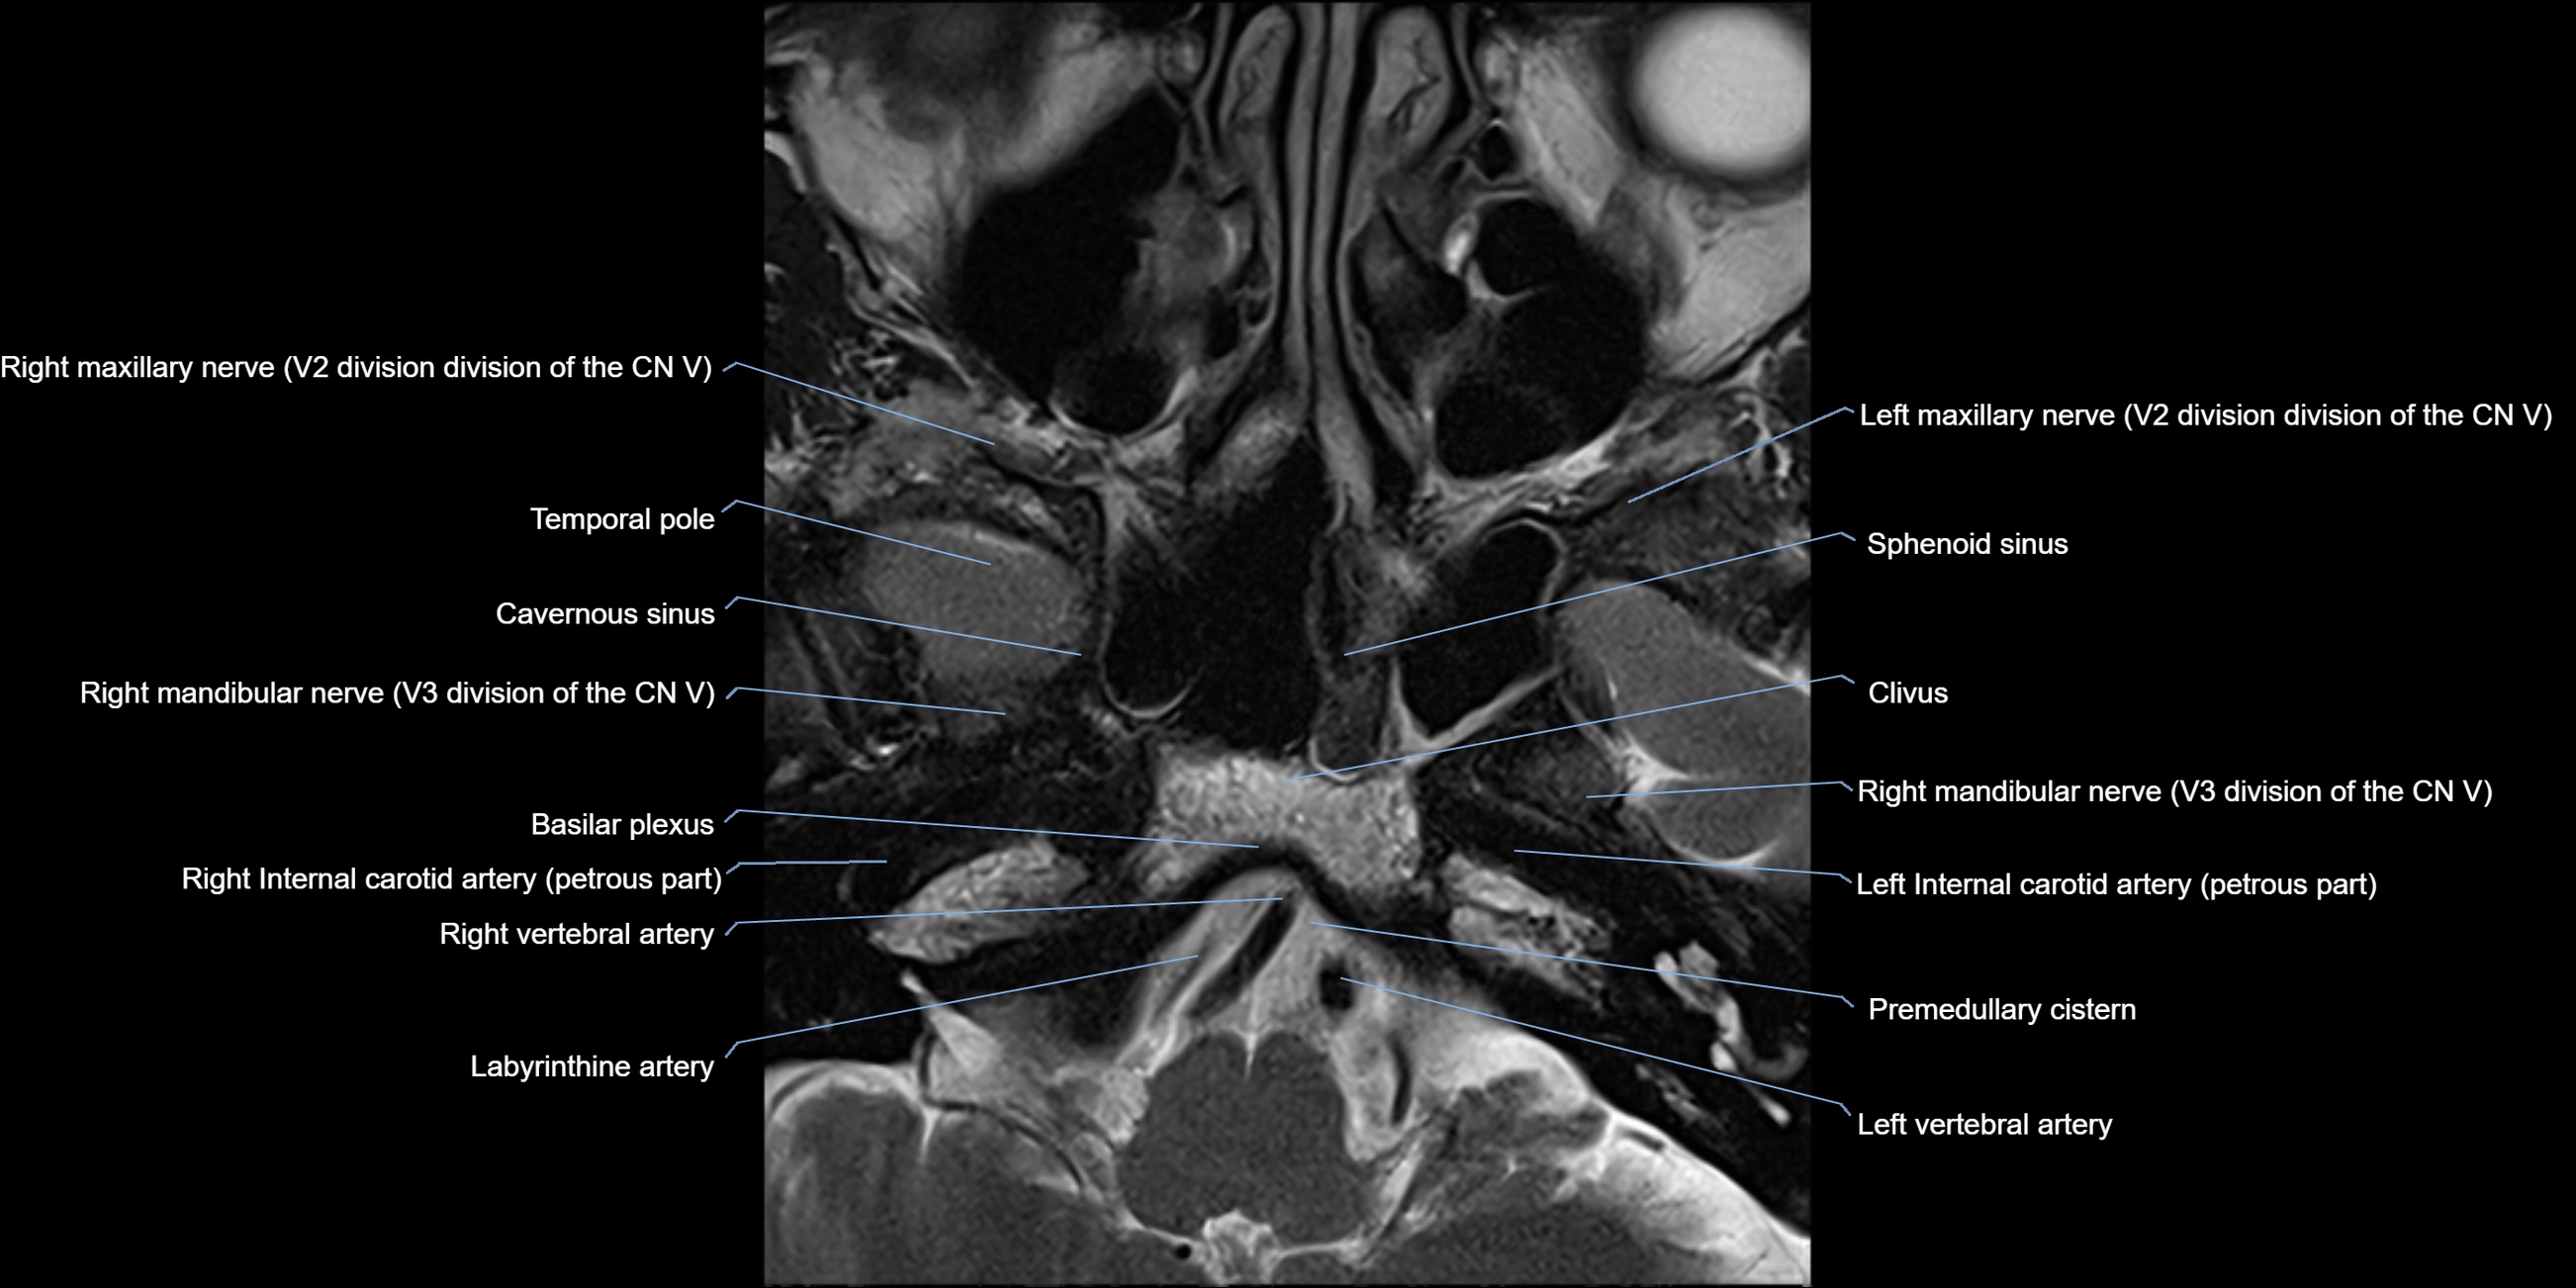

MRI Appearance

The abducens nerve is a small, thin, linear structure

Best visualized on high-resolution T2-weighted 3D MRI sequences (e.g., FIESTA or CISS)

Seen as a hypointense (dark) line running from the brainstem at the pontomedullary junction, traversing the prepontine cistern, and entering Dorello’s canal under the petrosphenoidal ligament, then into the cavernous sinus, and finally the orbit

May be challenging to visualize in standard MRI due to its small size

Pathology may be inferred by absence, displacement, or enhancement of the nerve

MRI images